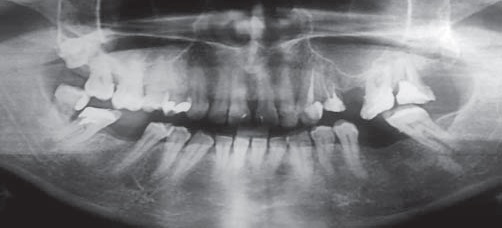

Результаты и их обсуждение. Установлено, что с возрастом частота встречаемости эндодонтопародонтальных поражений достоверно (р≤0,001) увеличивалась как у мужчин, так и у женщин (рис. 1). Так, в молодом возрасте эндодонтопародонтальные поражения диагностированы у 5 мужчин из 308 обследованных и у 4 из 147 обследованных женщин (рис. 2). Как правило, у этих пациентов тяжесть течения хронического генерализованного пародонтита обусловливалась сопутствующей соматической патологией (сахарный диабет первого или второго типа). При этом значение индекса КПИ было равно 1,92±0,21 у. е., что свидетельствовало о лёгкой степени поражения тканей пародонта. Показано, что у молодых женщин индекс гигиены полости рта равен 1,48±0,11 у. е. (хороший), у мужчин – 1,95±0,17 у. е. (удовлетворительный).

Рис. 2. Фрагмент ортопантомограммы: эндодонтопародонтальные поражения челюстей у пациентки К., 25 лет